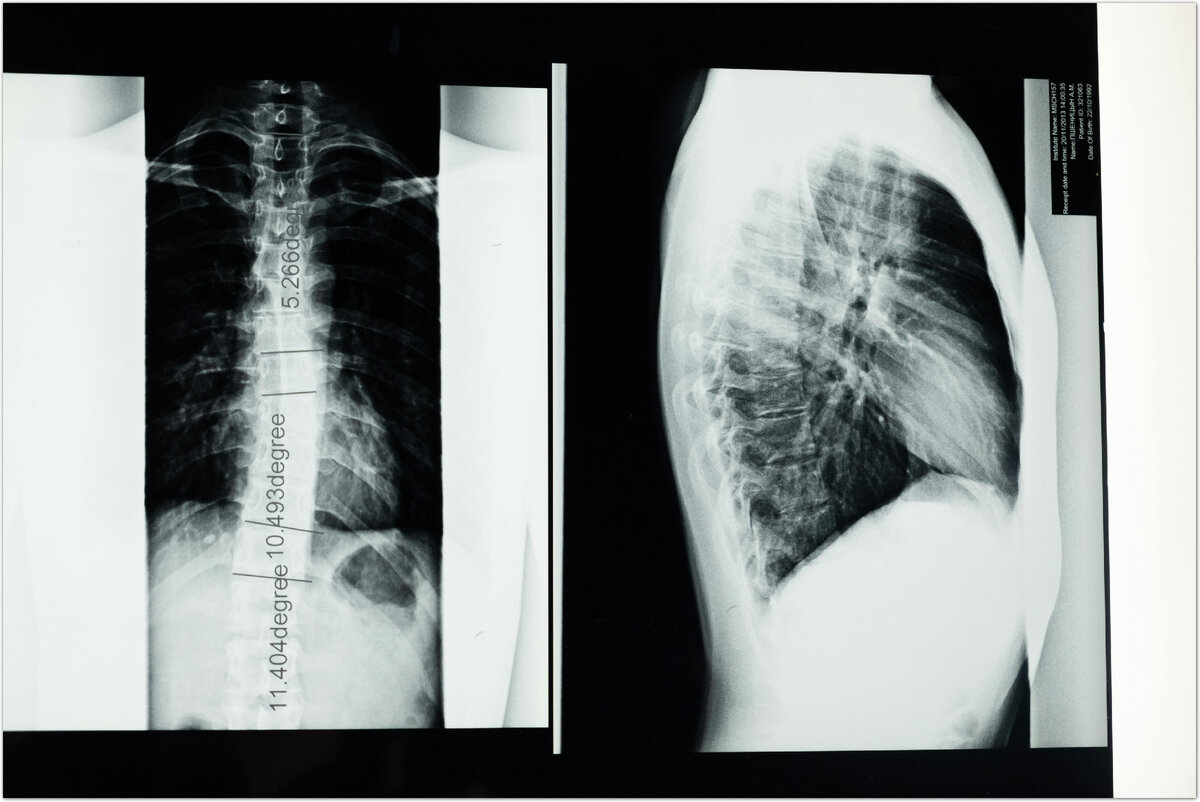

Гемангиома обычно развивается медленно и чаще всего не проявляет никаких симптомов. Только около 10% случаев новообразований сопровождаются болями. Часто эти опухоли обнаруживаются случайно при обследовании у невролога по поводу болей в спине. Назначается обследование рентген, МРТ или КТ. В заключении, кроме гемангиомы, часто описываются дегенеративные изменения позвоночного столба (например, остеохондроз, остеофиты, грыжи межпозвонковых дисков), которые действительно могут быть причинами болей.

Если опухоль большая и занимает более половины объема позвонка, то могут беспокоить боли